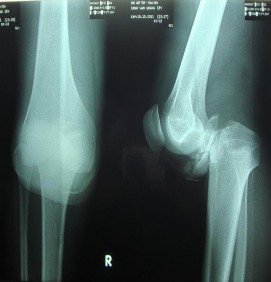

Theo Dương Đức Hùng (2005), [12] có một số đặc điểm cần lưu ý khi có tổn thương động mạch kèm theo đó là gãy xương quanh gối (gãy 1/3 dưới xương đùi, gãy đầu dưới xương đùi, gãy mâm chày, gãy 1/3 trên xương cẳng chân) và sai khớp gối có nguy cơ chèn ép vào động mạch khoeo (Ảnh 1.1); gãy xương, sai khớp di lệch lớn làm co kéo, căng giãn gây đứt hoặc rách động mạch đi sát xương; gãy xương hở với tổn thương phần mềm lan rộng có thể động mạch cũng bị đụng dập; bầm tím tụ máu lớn tăng dần ở trám khoeo sau gãy xương, sai khớp vùng này là dấu hiệu cần tìm tổn thương động mạch.

Ảnh 1.1: Hình ảnh sai khớp gối trái.

*Nguồn: theo Versier G. (2006)[120]